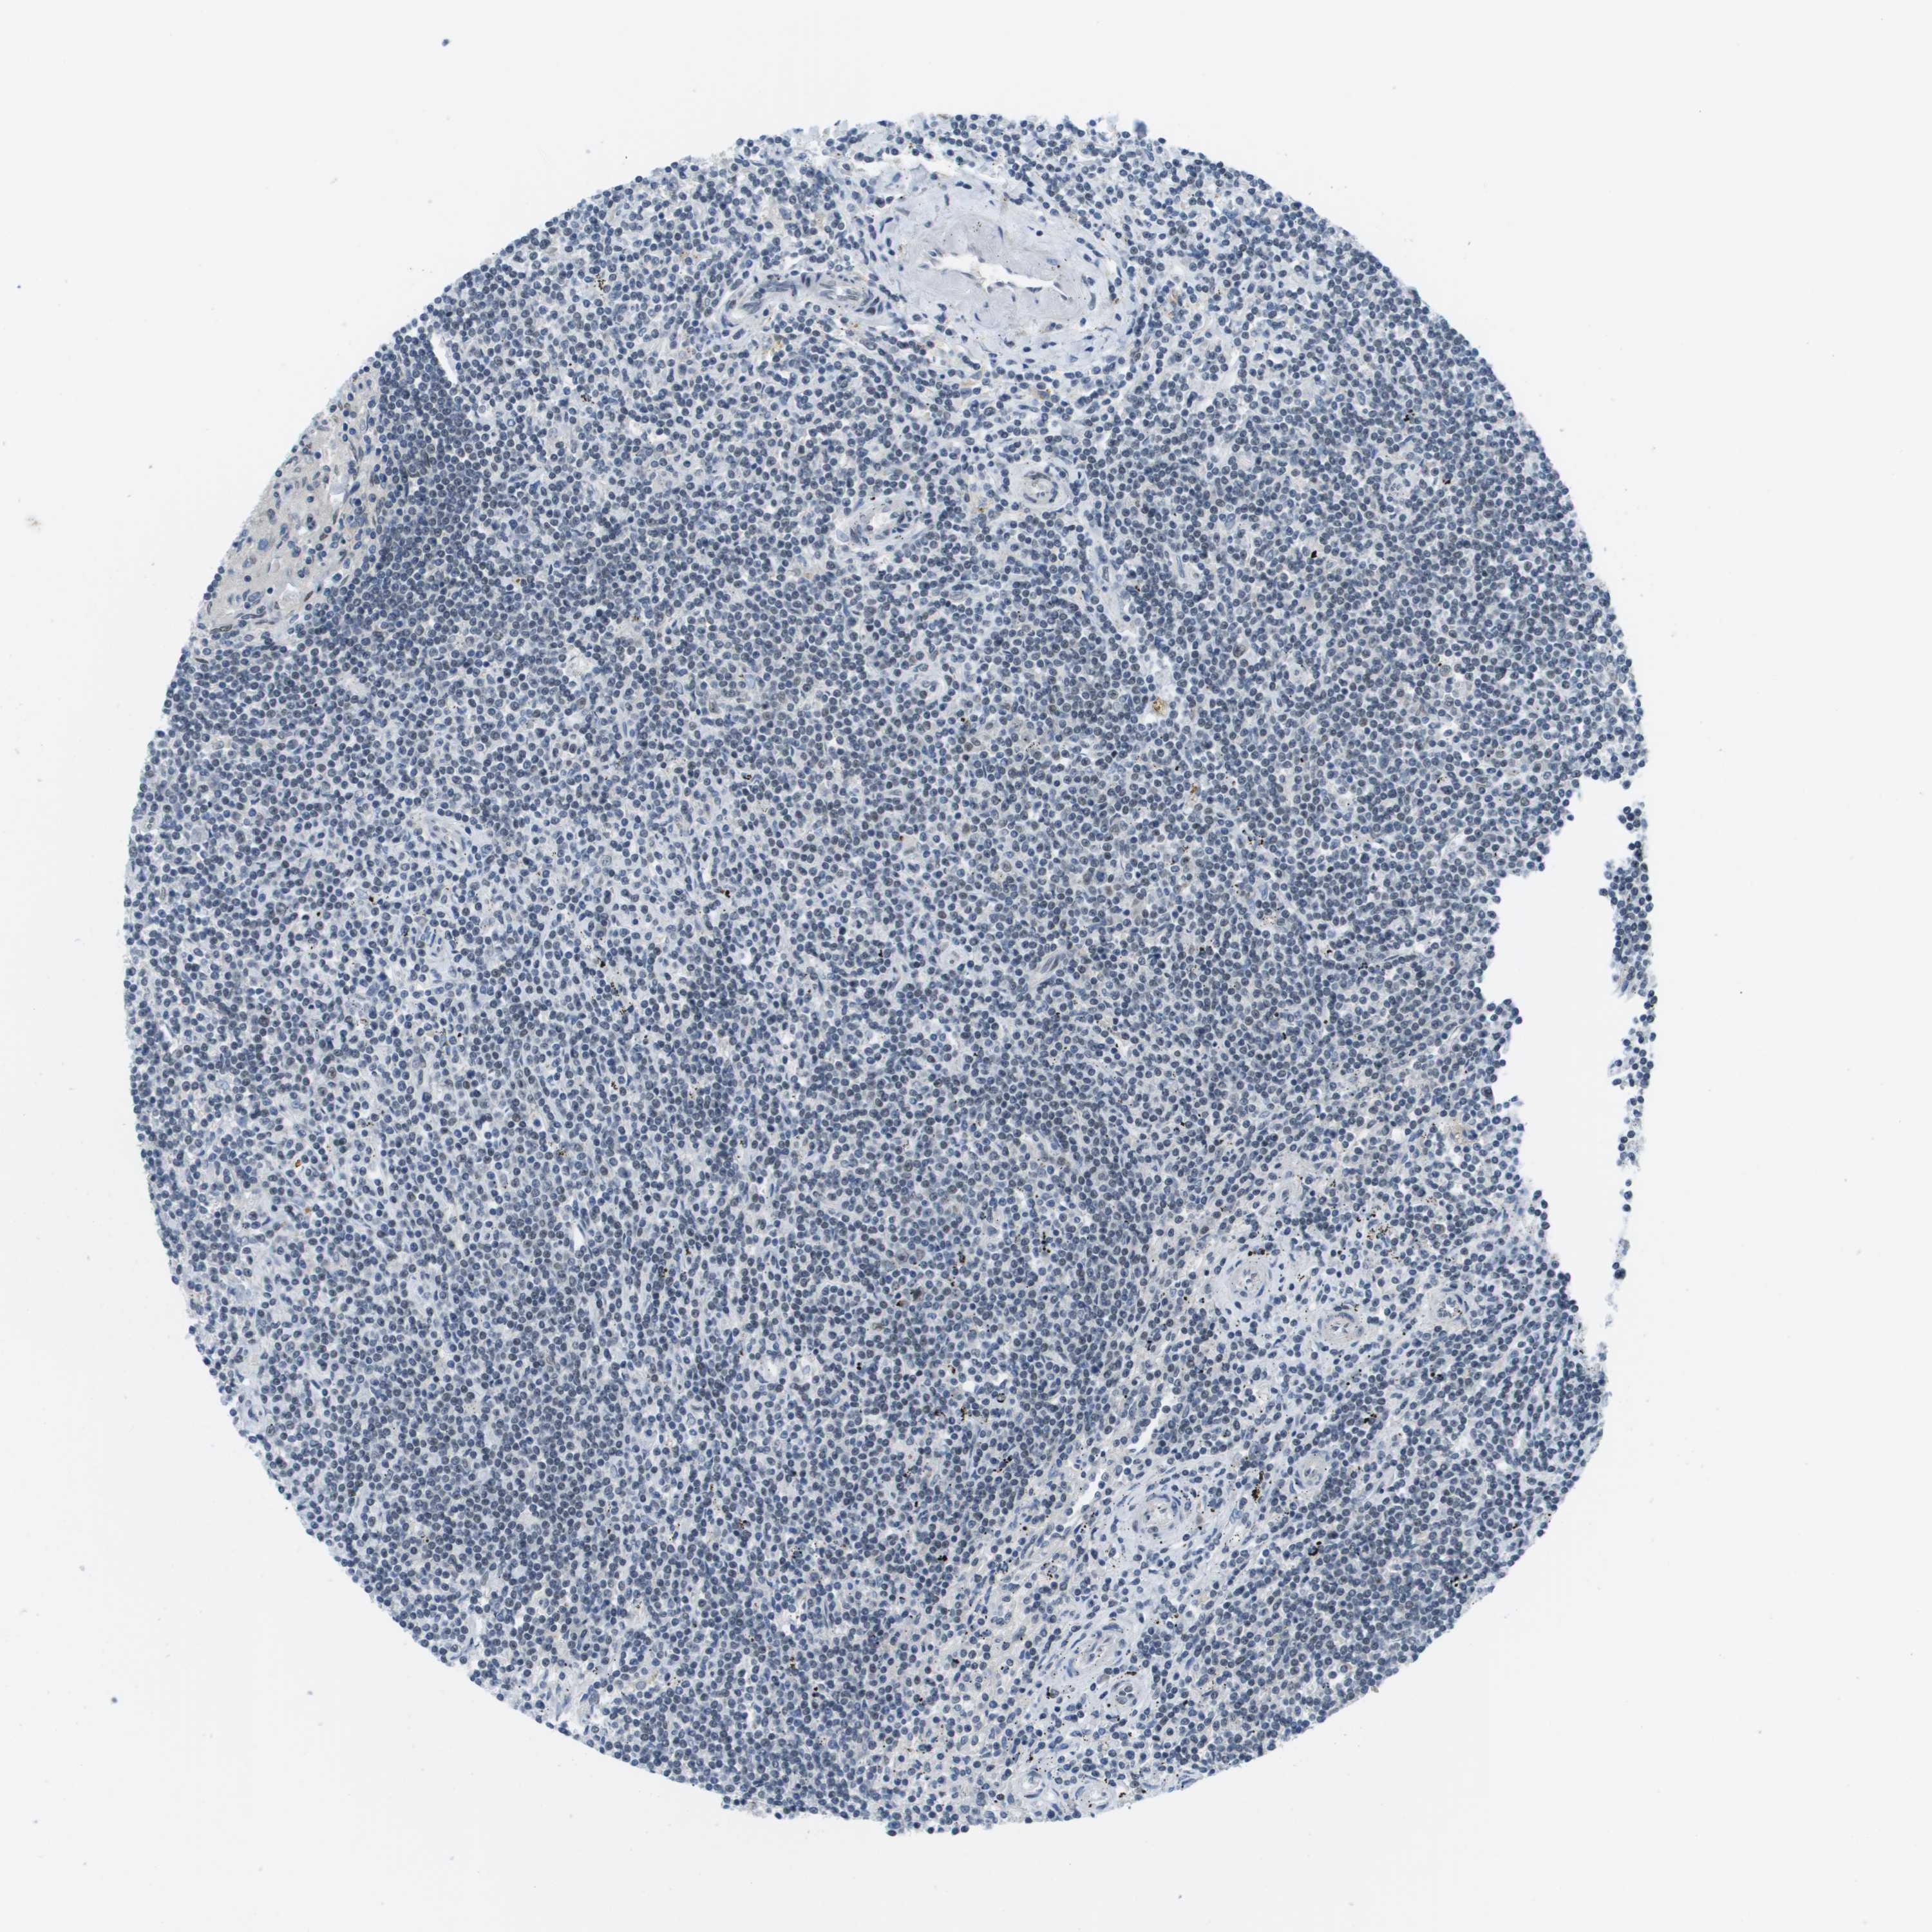

CANCER LYMPHOMA Show tissue menu

LYMPHOMA - Protein expressioni

A mouse-over function shows sample information and annotation data. Click on an image to view it in a full screen mode. Samples can be filtered based on level of antibody staining by selecting one or several of the following categories: high, medium, low and not detected. The assay and annotation is described here.

Each image is clickable and will lead to virtual microscopy that enables deeper exploration of all samples and also displays staining intensity scores, fraction scores and subcellular localization as well as patient and tissue information for each sample.

Antibody HPA016511

Staining

High

Medium

Low

Not detected

Intensity

Strong

Moderate

Weak

Negative

Quantity

>75%

75%-25%

<25%

None

Location

Nuclear

Cytoplasmic/membranous

Cytoplasmic/membranous,nuclear

Hodgkin's disease, NOS

Malignant lymphoma, non-Hodgkin's type, High grade

Malignant lymphoma, non-Hodgkin's type, Low grade